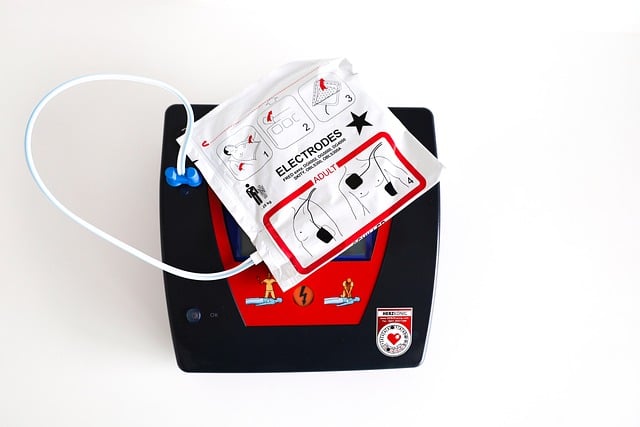

- AED(자동 심장 충격기) 사용

- AED가 준비되어 있다면 즉시 사용.

- AED의 지시에 따라 패드를 부착하고 전기 충격을 실시.